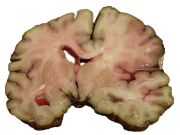

Intracerebral hemorrhage (ICH) is bleeding directly into the brain tissue, forming a gradually enlarging hematoma (pooling of blood). It generally occurs in small arteries or arterioles and is commonly due to hypertension, trauma, bleeding disorders, amyloid angiopathy, illicit drug use (e.g. amphetamines or cocaine), and vascular malformations. The hematoma enlarges until pressure from surrounding tissue limits its growth, or until it decompresses by emptying into the ventricular system, CSF or the pial surface. A third of intracerebral bleed is into the brain's ventricles. ICH has a mortality rate of 44 percent after 30 days, higher than ischemic stroke or even the very deadly subarachnoid hemorrhage.